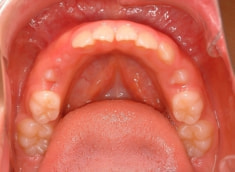

治療前